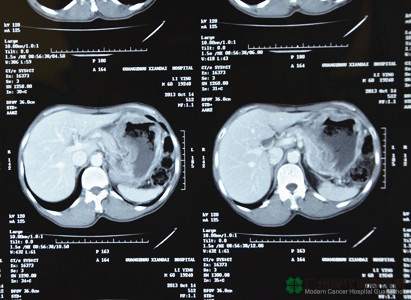

หลังจากที่มาถึงโรงพยาบาลมะเร็งสมัยใหม่กว่างโจว กลุ่มแพทย์จากหลากสาขา (กลุ่ม MDT) ก็ได้ดำเนินการตรวจให้หลี่อิงทันทีเพื่อเตรียมพร้อมในการรักษาภายหลัง ผลการตรวจบอกว่าหลี่อิงเป็นมะเร็งกระเพาะอาหารระยะสุดท้าย กลุ่ม MDT คำนึงถึงว่าสุขภาพเขาค่อนข้างอ่อนแอ จึงเลือกวิธีการที่ค่อนข้างจะครบรอบด้านให้กับเขา และค่อยๆ บรรเทาอาการของเขาทีละขั้นๆ กลุ่ม MDT ใช้วิธีการรักษาเฉพาะจุดผ่านหลอดเลือดก่อน โดยนำยาเข้าไปทางหลอดนำทางจากหลอดเลือดแดงฉีดเข้าไปที่ภายในก้อนมะเร็งที่กระเพาะอาหารโดยตรง อุดช่องทางอาหารของมะเร็ง และยังใช้วิธีการใช้ความเย็น การใช้เซลล์ภูมิคุ้มกันบำบัดร่วมกันเพื่อทำให้เซลล์มะเร็งแข็งตัว และในขณะเดียวกันก็เพิ่มภูมิคุ้มกันร่างกายให้กับหลี่อิงด้วย และเมื่อผ่านการรักษาอย่างต่อเนื่องโดยกลุ่ม MDT อาการของหลี่อิงก็ได้รับการควบคุม ก้อนเนื้อก็มีขนาดเล็กลงด้วย

มะเร็งกระเพาะอาหาร

หลังการรักษา